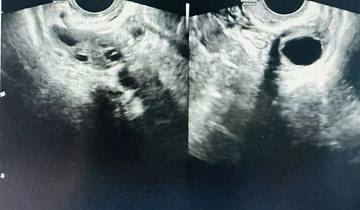

●做B超监测

去医院做B超声监测排卵,除了可以测量排卵日,还可以测量卵泡的具体大小,是一种更直观、更准确的排卵监测方法。

四川省生殖健康研究中心附属生殖专科医院正在投入使用的三星WS80A 超声诊断系统属于世界先进仪器设备,通过以程璐主任为学科带头人的拥有多年影像临床经验的超声科团队操作,能为大家提供更精准的检查数据,帮助早日收获圆满!